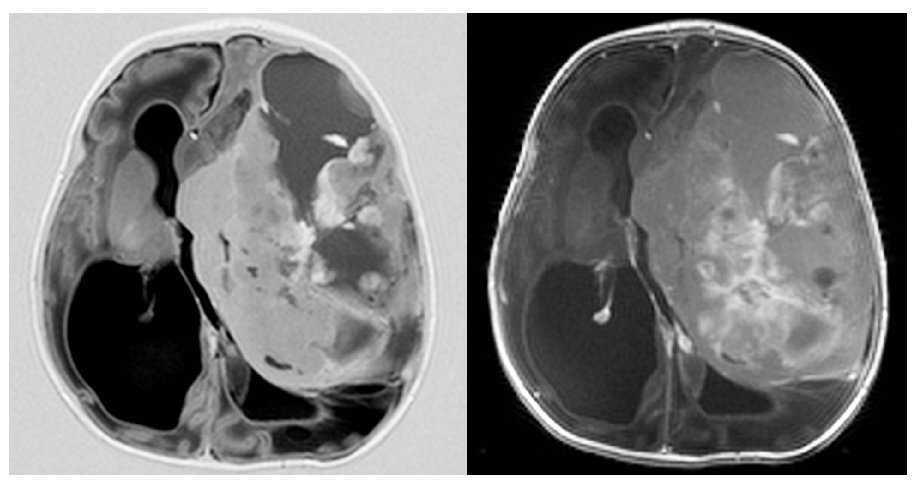

Gestante en el séptimo mes del embarazo. En ecografía de control se detecta hidrocefalia.

Fig. 4.